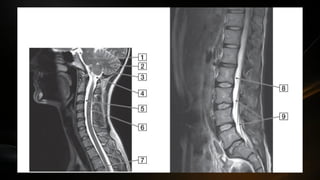

Medula espinal

• Parte del SNC ocupa el conducto vertebral protegida por las meninges

raquídeas

• Se extiende desde la articulación atlantooccipital hasta el borde

superior de la segunda vertebra lumbar (L2)

• En el extremo caudal la medula espinal termina en forma de cono

(cono medular) de esta porción sale el filum terminale que desciende

• La medula espinal en su trayecto muestra

dos engrosamientos fusiformes: las

intumescencias cervical y lumbrosacra

• La intumescencia cervical se extiende

desde la tercera vertebra cervical a la

segunda torácica

• La intumescencia lumbrosacra desde la

novena vertebra torácica hasta la primera

lumbar